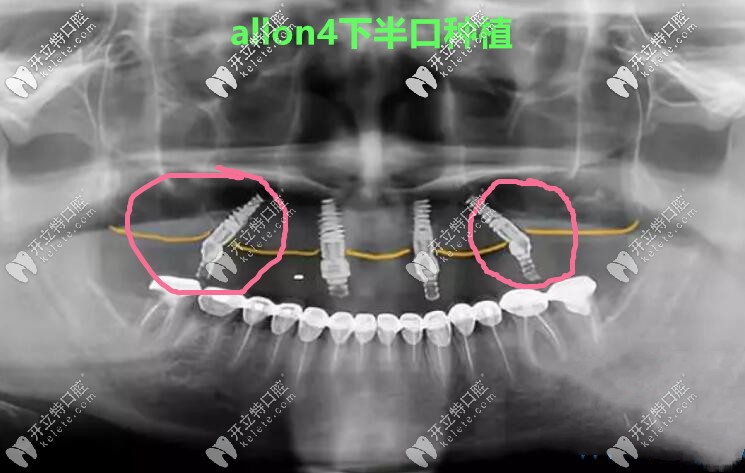

做allon4下半口種植牙真人案例CT照↓↓↓

做allon4下半口種植牙真人案例CT照

張海波院長說,它倆明顯的區(qū)別就是,allon4/6有2顆植體是斜著的,因?yàn)楸荛_了神經(jīng)管和上額竇孔腔,所以主要針對的是那些牙槽骨非常糟糕,無法常規(guī)種植的人。